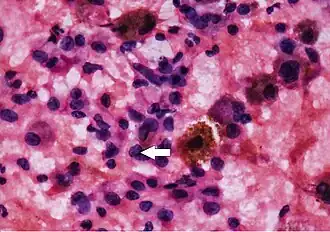

Thyroid cytopathology of Bethesda category III with clotting artifact

Thyroid cytopathology of Bethesda category III with clotting artifact Category IV

Category IV Category V with intranuclear cytoplasmic inclusion

Category V with intranuclear cytoplasmic inclusion Category V with nuclear groove (arrow)

Category V with nuclear groove (arrow) Cytopathology suspicious for Hürthle cell neoplasm (Bethesda category IV, rather than Hürthle cell hyperplasia), Pap stain.[14]

Cytopathology suspicious for Hürthle cell neoplasm (Bethesda category IV, rather than Hürthle cell hyperplasia), Pap stain.[14]